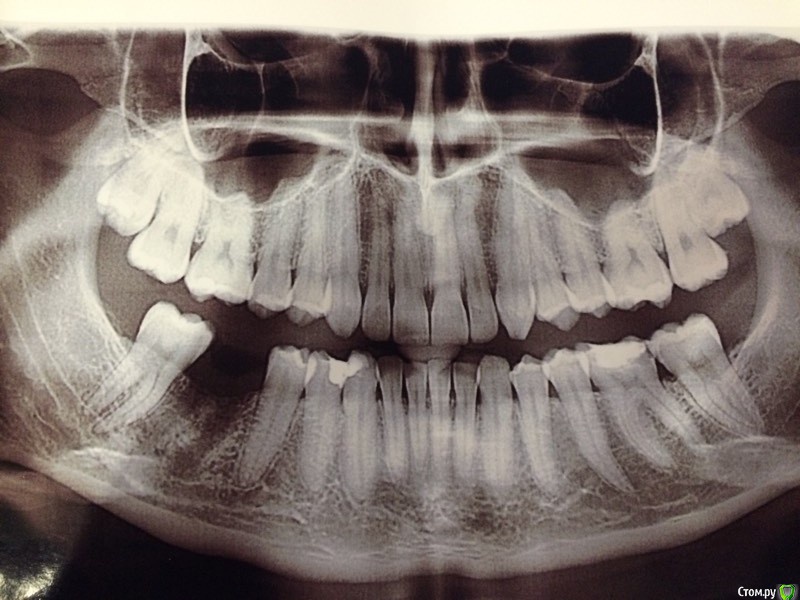

flyfli Опубликовано 23 апреля, 2018 Поделиться Опубликовано 23 апреля, 2018 Уважаемые доктора, подскажите мне ,пожалуйста, нужно ли что- то еще лечить из оставшихся зубов? Ссылка на комментарий

red_butler Опубликовано 24 апреля, 2018 Поделиться Опубликовано 24 апреля, 2018 я бы очно посмотрел зубы 3.6 3.7 И удалил бы восьмерки Ссылка на комментарий

flyfli Опубликовано 24 апреля, 2018 Автор Поделиться Опубликовано 24 апреля, 2018 Скажите, что Вы примерно видите на снимке с 6 кой??Сходила на консультацию один врач сказал: там кариес под пломбой и надо ставить вкладку циркониевую, второй врач сказал, что там киста дистальная у корня и что нужно вскрывать кломбу лечить канал и закрывать новой пломбой.Не знаю что и делать и что в конце концов с этим зубом.... Ссылка на комментарий

red_butler Опубликовано 24 апреля, 2018 Поделиться Опубликовано 24 апреля, 2018 Похоже на кариес на боковых поверхностях обоих зубов Ссылка на комментарий

flyfli Опубликовано 4 мая, 2018 Автор Поделиться Опубликовано 4 мая, 2018 подскажите,как быть на эту 6 ку лучше поставить пломбу или спилить все нафик и поставить коронку керамическую? Ссылка на комментарий

DmitrySH Опубликовано 5 мая, 2018 Поделиться Опубликовано 5 мая, 2018 подскажите,как быть на эту 6 ку лучше поставить пломбу или спилить все нафик и поставить коронку керамическую? Надо очно оценивать. может быть не коронку, а керамическую вкладку. Зависит от кол-ва оставшихся тканей зуба Ссылка на комментарий